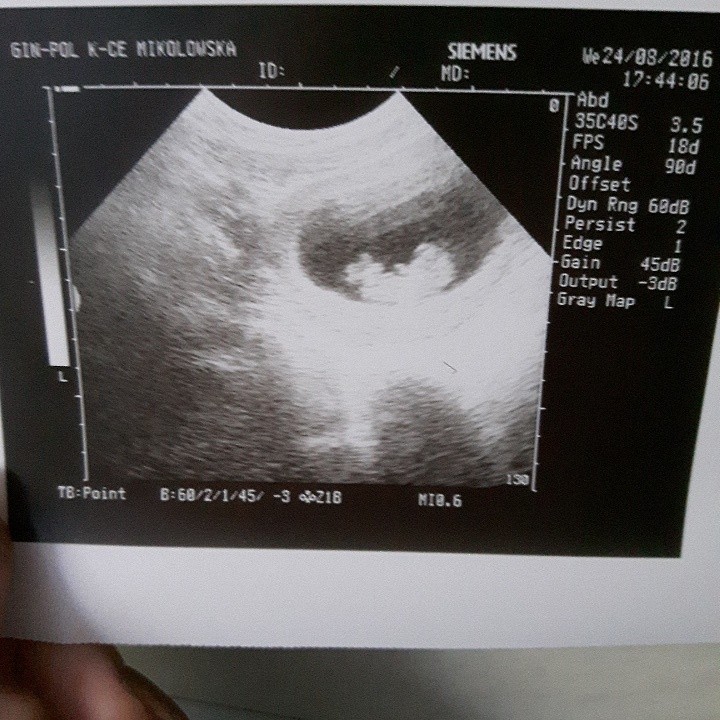

To i moja kolej. Na chwilę obecną spodziewam się bliźniąt jednojajowych! Mają po 3 mm i jednemu już bije serduszko. Za dwa tygodnie wizyta kontrolna i założenie karty ciąży. Oby wszystko było dobrze. A tu zdjęcie. Przy pecherzyku żółtkowym widać dwa malutkie przecinki jeden pod drugim